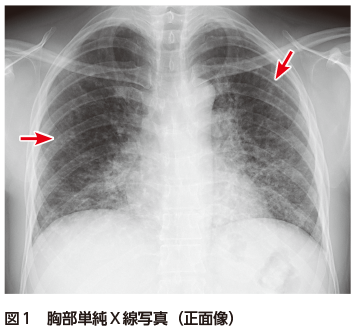

NMC Diagnosis。0b3b59392e9eaf6a38d2ac37cd75fc。間質性肺炎 | 印西そよかぜ内科・呼吸器内科。画像診断 Vol.41 No13. 特集『なぜによくわからない間質性肺炎。「肺炎の画像診断と最新の診療」藤田次郎定価: ¥ 12,540#藤田次郎 #本 #BOOK #健康 #医学